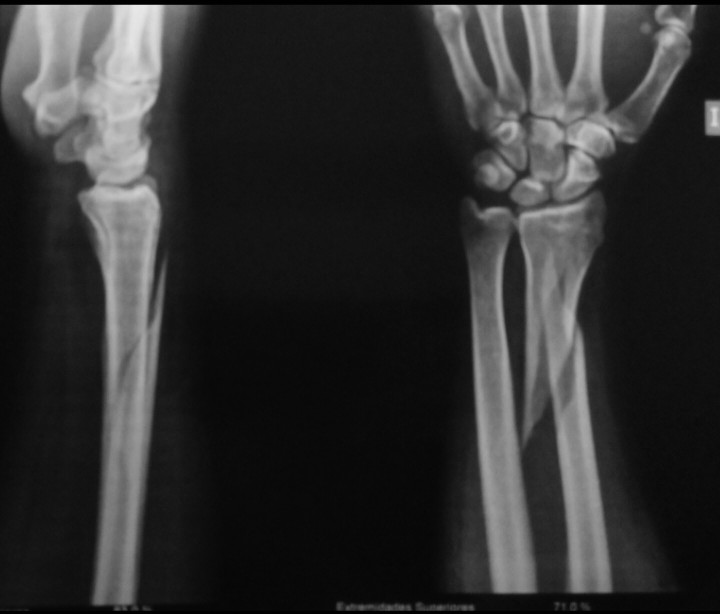

Перелом лучевой кости

Уважаемые коллеги, прошу совета по погружному остеосинтезу перелома лучевой кости.

Необходимо выполнить рентгенограммы проксимального отдела предплечья. Доступ лучше передний: репозиция, межфрагментарная фиксация двумя винтами, нейтрализующая реконструктивная длинная пластина с угловой стабильностью для дистального отдела лучевой кости. Если тыльный доступ, то также, но прямая пластина с угловой стабильностью, но возможно маловато будет винтов в дистальном отломке.

Согласен с Вами, но что касается выбора металлоконструкции, я бы предпочёл длинный DVR. Обосновано это тем, что судя по представленным рентгенограммам, дистальный отломок очень небольшой и реконструктивная пластина позволит провести не более 2 винтов, что на мой взгляд недостаточно.

Добрый день. Изолированный спиральный перелом метадиафиза лучевой кости? Не верю. Не верю, что изолированный.